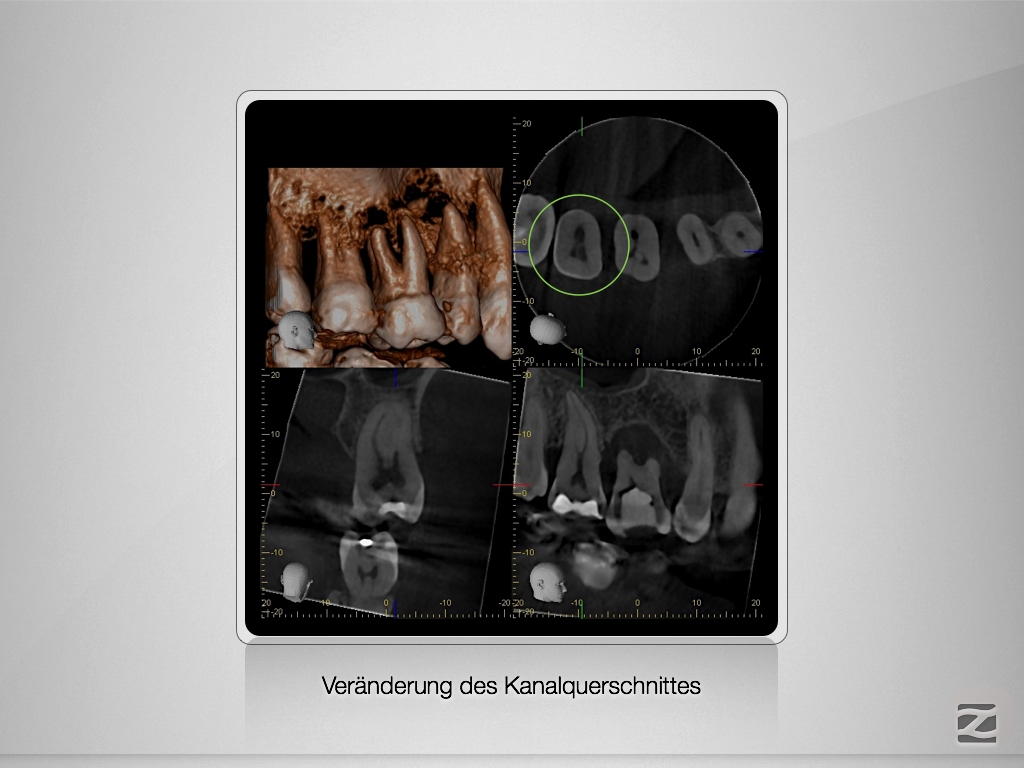

17D.003

Gewusst, wo’s lang geht.